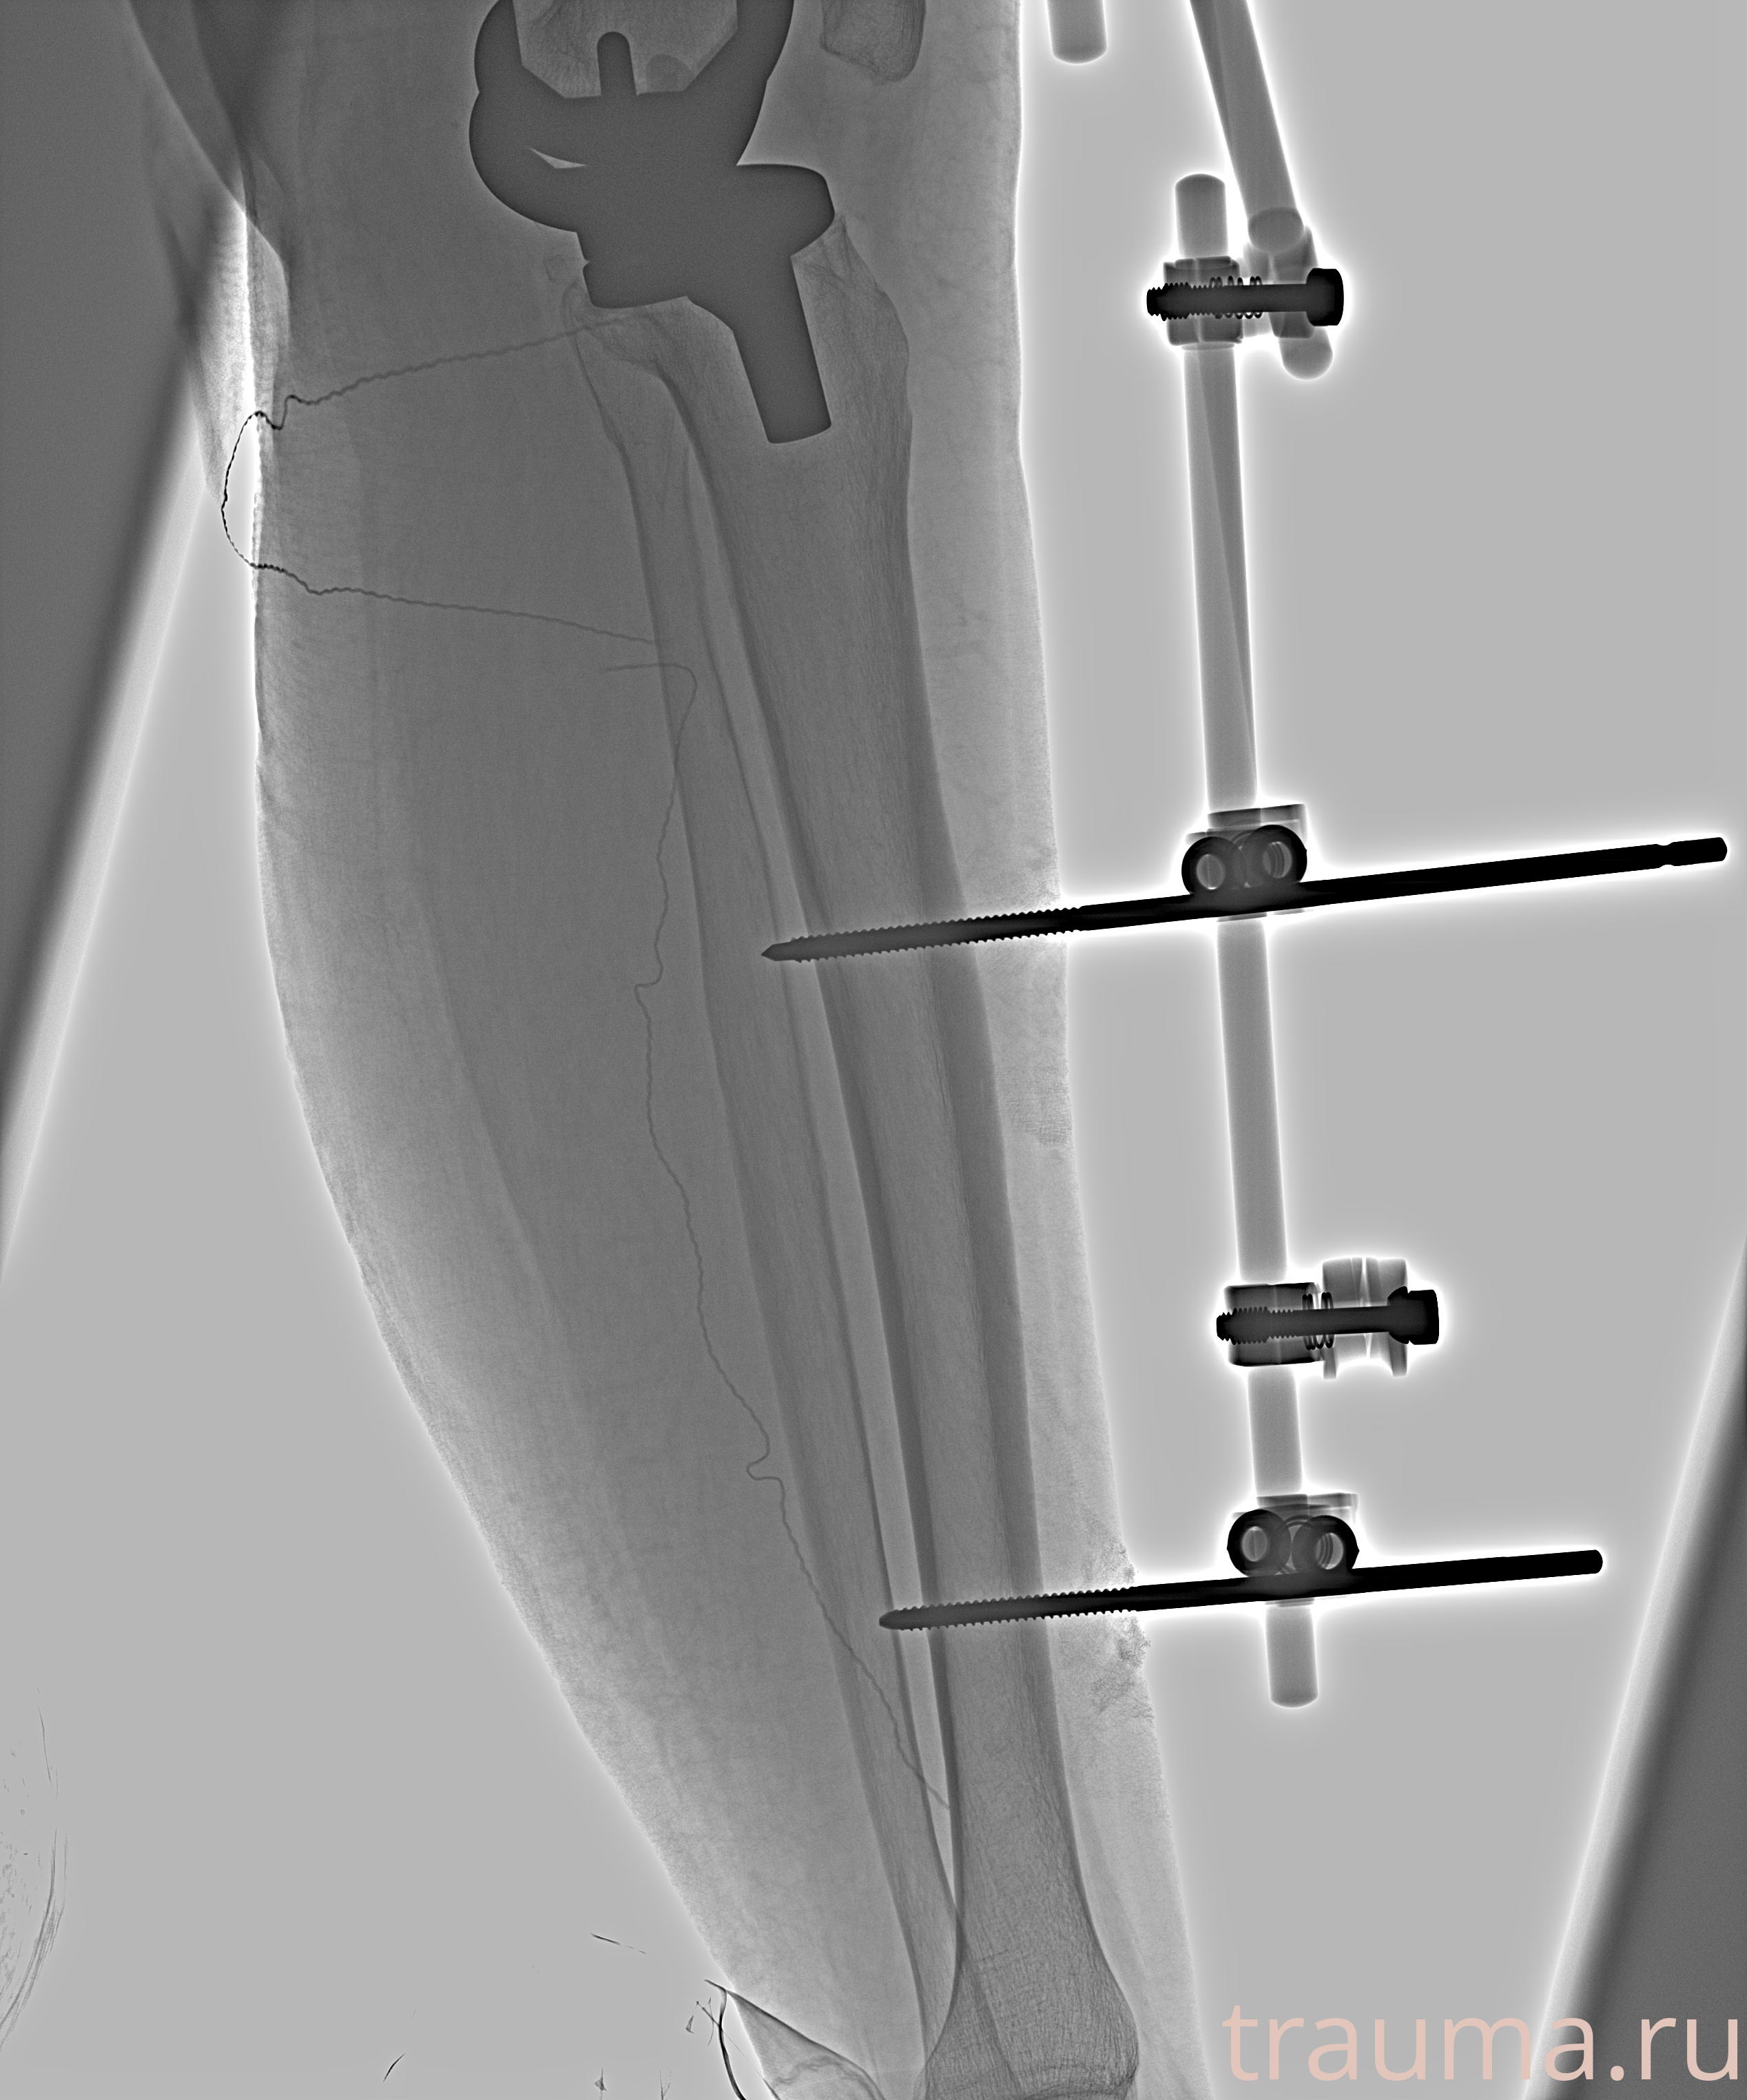

Видео КТ после вправления и наложения АНФ